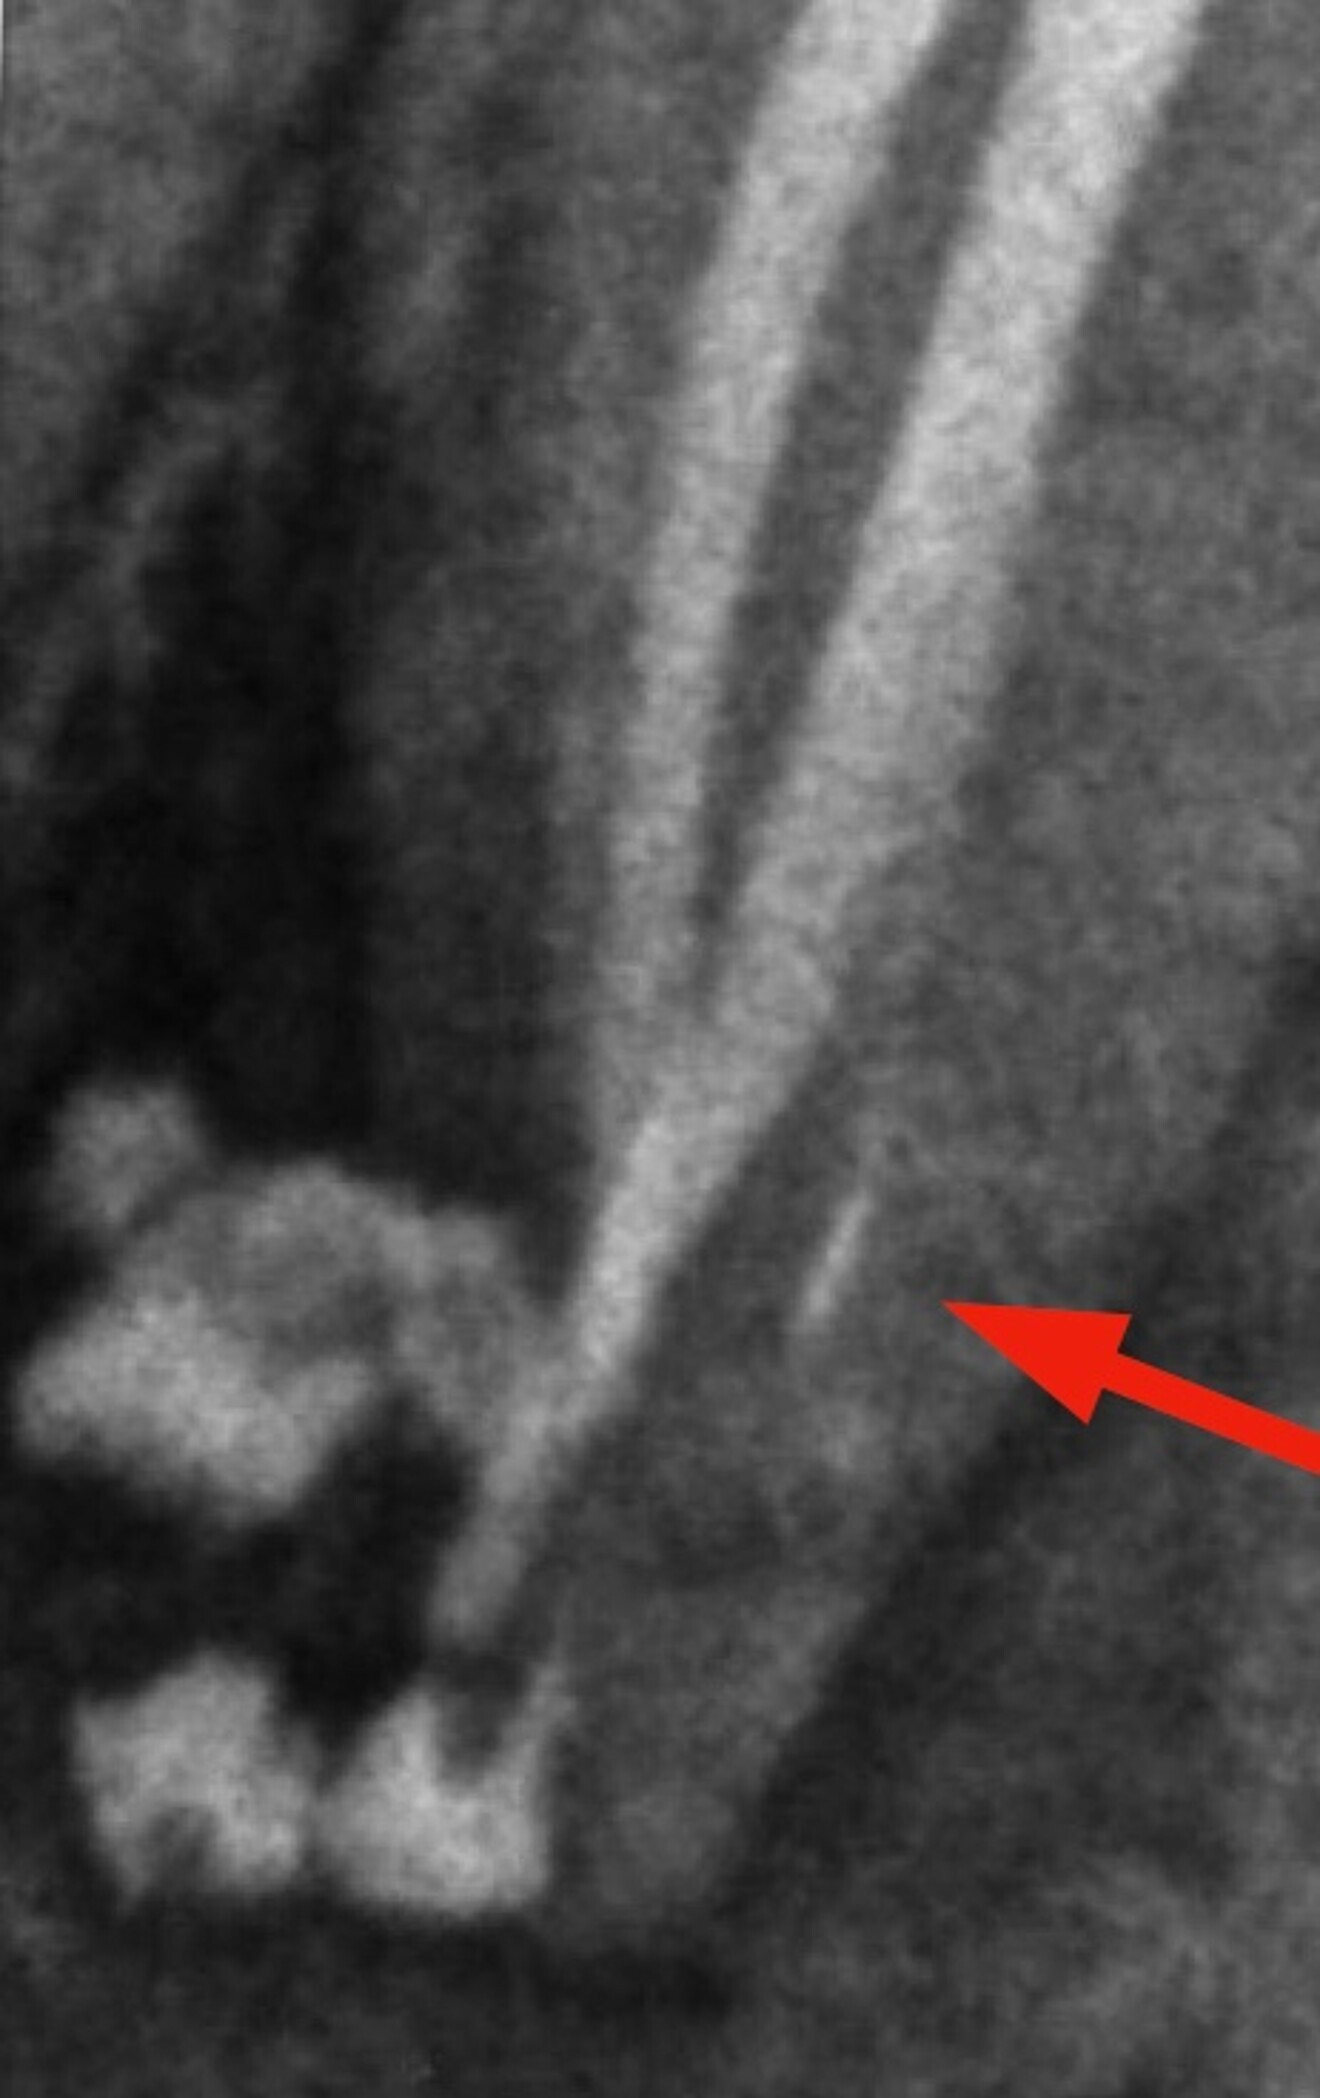

Literature has documented multiple variations in canal configurations of the lower bicuspid. The current case shows a variation in Vertucci Classification Additional type 1-3-1.

The case was treated and the lingual canal was missed out leading to a large periapical lesion and drainage. 3-D imaging revealed a single root and a missed lingual canal. The internal anatomy was complex, and if you observe the post-operative radiograph closely, it shows the presence of a small lateral canal with an independent exit.